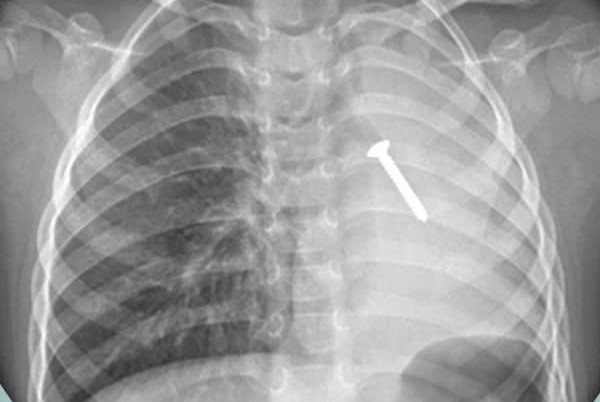

Sau bữa cơm trưa khoảng 30 phút, một cháu bé ở Nghệ An đột ngột tím tái, ngưng thở. Tại bệnh viện, hình ảnh chụp X-quang cho thấy, phổi trái của bệnh nhi có chiếc đinh vít, kích thước khoảng 30 x 5mm.

Hình ảnh chụp X-Quang cho thấy chiếc đinh vít sắc nhọn nằm ở vị trí phổi trái của bệnh nhi.

Tại đây, kết quả chụp X-Quang cho thấy có một hình ảnh dị vật cản quang phổi trái (hình dạng như chiếc đinh vít), kích thước khoảng 30 x 5mm, mất hoàn toàn thông khí phổi trái. Đây là một trường hợp dị vật đường thở nguy hiểm, nên quyết định nội soi phế quản cấp cứu.